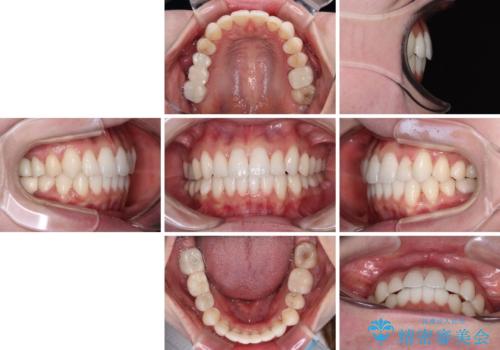

ワーキングホリデー前にきれいな歯列に

矯正治療後半に奥歯の補綴治療が必要な歯にはオールセラミッククラウンを装着し、インビザラインで最終的に仕上げることとしました。

海外に行く前に口腔内環境を整えることができ、患者様には大変満足していただきました。